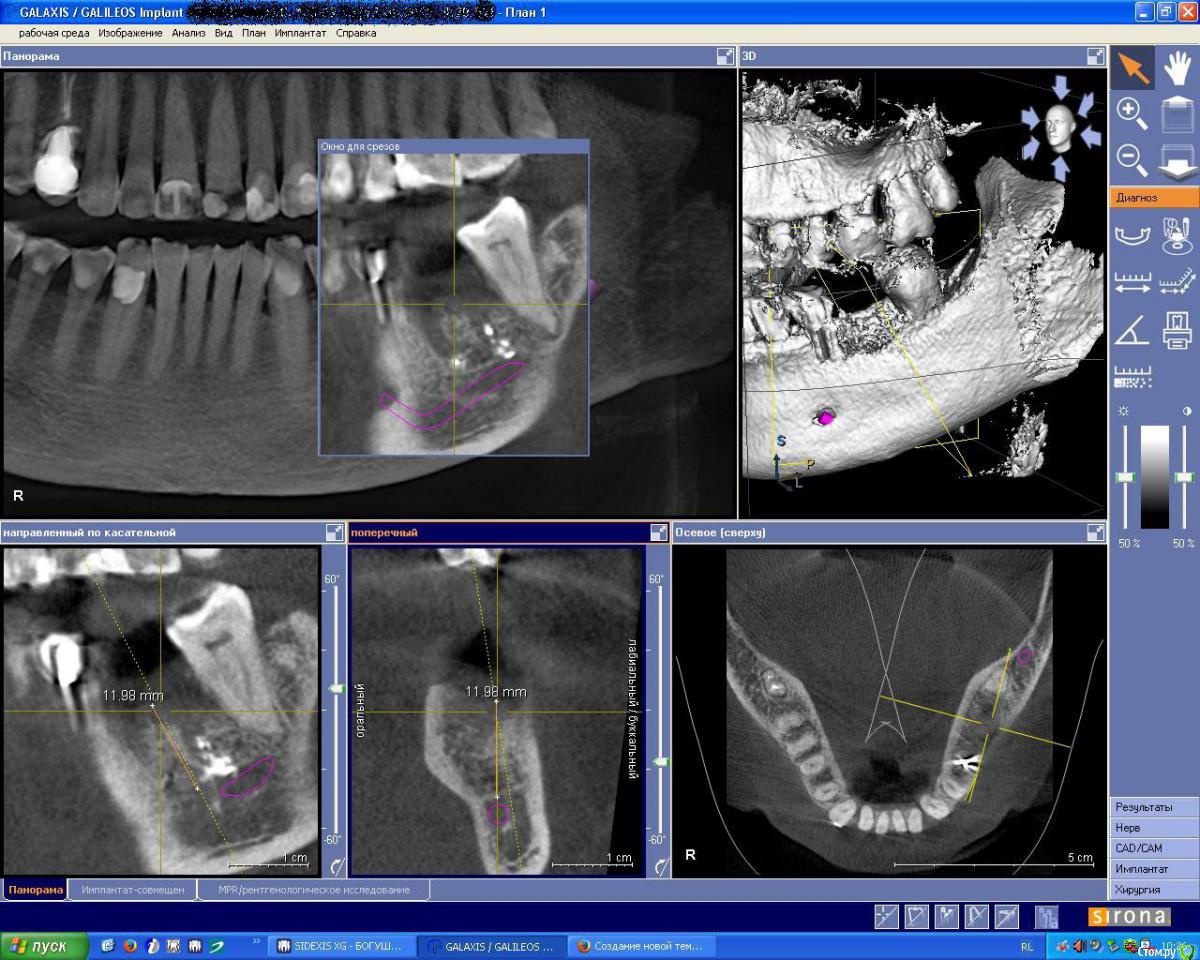

IshIm0 Опубликовано 12 августа, 2015 Поделиться Опубликовано 12 августа, 2015 (изменено) Добрый день коллеги, помогите определиться с тактикой лечения пациента на имплантацию. 18.04.15 Пациентке удалён зуб 36 с выпиливанием корней и полуторачасовым мучением - зуб буд-то анкилозировался с костью. Заживало всё не айс, сгусток вымылся, пища забивалась. Прошло 4 месяца - в полости рта как ни странно все хорошо, лунка под плотной бледно-розовой слизистой, кость при пальпации плотная, широкая. Жалоб не предъявляет - говорит давай имплантат, настроена позитивно. Далее на КТ определяется оставшийся пломбировочный материал, в лунке дистального корня зуба 36 пломбировочный материал лежит фактически на ничнежелюстном нерве. Планирую поставить ICX Ø 4,1 x 10mm, в межкорневую перегороду, уйти немного язычнее, но опасаюсь не даст ли мне этот пломбировочный материал воспалительную реакцию в последствии.Интересуют ваши мнения по поводу данной клинической картины!Позиционирование имплантата на КТ верно? (на КТ Astra 4.5 х 9 mm) Изменено 12 августа, 2015 пользователем IshIm0 Ссылка на комментарий